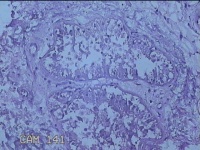

右侧腋窝皮肤

性别

女

年龄

25岁

临床诊断

双侧腋臭

一般病史

发现双侧腋下异味7年。

标本名称

大体所见

灰白暗红色梭形皮肤组织7x2.3x0.8cm一块,表面糜烂,切面灰白暗红色,质软。